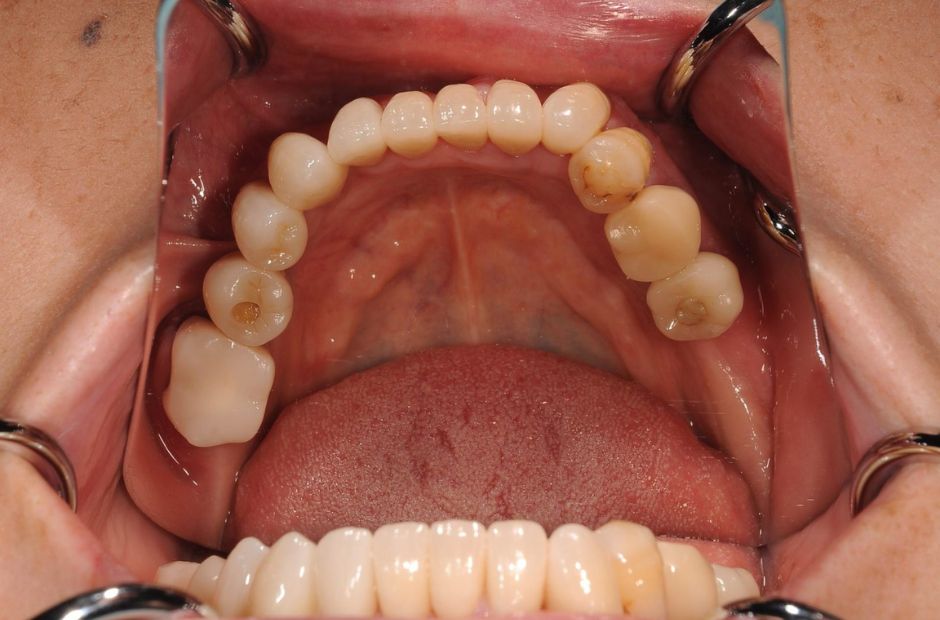

case.01

インプラントで口腔機能の改善

中年の患者様がインプラント治療を希望し来院されました。数本の歯を失っていたため、インプラントを用いて噛む力と審美性を回復しました。治療により、患者様は食事の楽しみを取り戻し、自信を持って笑顔を見せるようになりました。